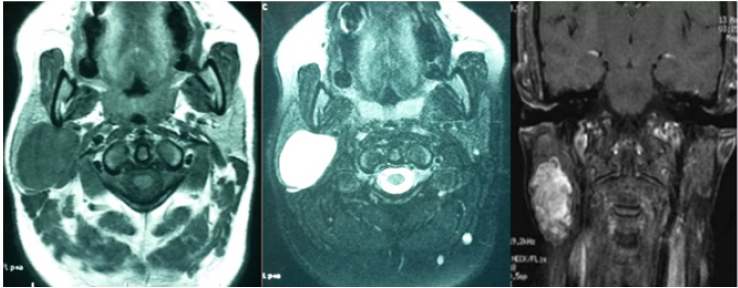

Benign tumors account for 80% of all of our patients, dominated mainly by pleomorphic adenoma followed by whartin tumor. There were 8 cases of cancer that were of a diverse nature (Table 1). Cervical ultrasound was performed in 18 patients. Computed tomography in 20 patients (44% of the cases), generally in the face of very large tumors initially in order to specify their depth extension. Magnetic resonance imaging was realized for 39 patients (Figures 1 & 2). We studied the morphological and functional MRI criterias of the pleomorphic adenomas of our patients, warthin tumors and malignant tumors, then we established different criterias associations and their predictability of the final histological result of the tumor.

Figure 1: MRI image in axial section in T1, T2, T1C + weighted sequences of a pleomorphic adenoma of the parotid.

The Association: Low signal intensity on T1, high signal intensity on T2, apparent diffusion coefficient superior to 1,5 and positive enhancement after injection of contrast product, was significant in predicting the histological diagnosis of pleomorphic adenoma, with a specificity 100% of and a sensibility of 83%. The association: low signal intensity on T1, irregular lesion limits, apparent diffusion coefficient inferior to 1 and extra parotid extension, was significant in predicting the histological diagnosis of malignant tumors with a specificity of 100% and a sensibility of 67%. However no statistically significant association was found for the cases of warthin tumors. The MRI histological correlation predicting the benignity or malignancy of the parotid tumor showed that for a total of 39 MRI results, the correlation was statistically significant (p< 0.001) with a sensibility of 100% and specificity of 94,1%. Furthermore, the MRI histological correlation predicting the diagnosis of pleomorphic adenoma was statistically significant (p< 0.001) with a sensibility of 90% and specificity of 86,7%.